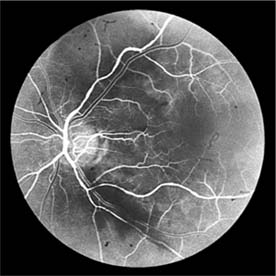

Figure 15-10

Figure 15-10: Accelerated hypertension. Fluorescein angiogram in a young man showing arteriolar constriction, dilation of capillaries with microaneurysms, and areas of closure. Marked disk edema is present.

In contrast, elderly patients with arteriosclerotic vessels are unable to respond in this manner, and their vessels are thus protected by the arteriosclerosis. It is for this reason that elderly patients seldom exhibit florid hypertensive retinopathy (Figure 15-11).

Figure 15-11

Figure 15-11: Accelerated hypertension. Fluorescein angiogram in an elderly wom.an showing marked arteriolar constriction and irregularity but few signs of florid retinopathy.

Fluorescein angiography has made possible accurate documentation of these microcirculatory changes. In young patients with hypertension, arteriolar attenuation and occlusion are seen, and capillary nonperfusion can be verified in relation to a cotton-wool spot, which is surrounded by abnormal dilated capillaries and microaneurysms with increased permeability on fluorescein angiography.

Resolution of the cotton-wool spots and the arteriolar changes occurs with successful hypotensive therapy. In elderly patients, the underlying arteriosclerotic changes are irreversible.